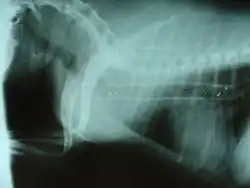

Symptoms include a cough (often called a "goose honk cough" due to its sound), especially when the dog is excited. This cough is usually paroxysmal in nature. Other symptoms include exercise intolerance, respiratory distress, and gagging while eating or drinking. Tracheal collapse is easily seen on a radiograph as a narrowing of the tracheal lumen. Treatment for mild to moderate cases include corticosteroids, bronchodilators, and antitussives. Medical treatment is successful in about 70 percent of tracheal collapse cases.[4] Severe cases can be treated with surgical implantation of a tracheal stent (inside or outside of the trachea) or prosthetic rings. Extraluminal (outside the trachea) stenting is generally used only for tracheal collapse in the neck region. Intraluminal stenting has shown more promise for success with intrathoracic cases, especially using nitinol, a type of shape memory alloy composed of nickel and titanium. Potential problems include stent migration and fracture.[5]